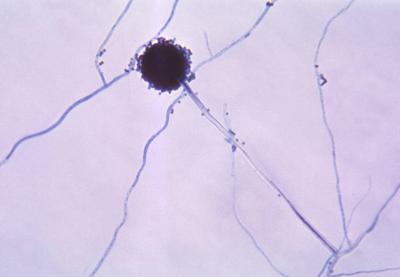

दिल्लीत नव्या फंगसमुळे होणाऱ्या मृत्यूंमुळे चिंतेत भर पडली आहे. एम्समध्ये दोन रुग्णांना एस्परजिलियस लेंटुलस नावाच्या फंगसची लागण झाली. या प्रकारच्या फंगसवर कोणत्याही औषधाचा परिणाम होत नाही.

क्रॉनिक ऑब्स्ट्रक्टिव पल्मोनरी डिजीजचा सामना करत असलेल्या दोन्ही रुग्णांचा उपचारादरम्यान मृत्यू झाला. एस्परजिलियस लेंटुलस फुफ्फुसावर परिणाम करतं. २००५ मध्ये वैद्यकीय जगताला या फंगसची औषध पटली. तेव्हापासून आतापर्यंत अनेक देशांमध्ये एस्परजिलियस लेंटुलसचे रुग्ण आढळून आले आहेत.

भारतात पहिल्यांदाच एस्परजिलियस लेंटुलसचे रुग्ण आढळून आले आहेत. इंडियन जर्नल ऑफ मेडिकल मायक्रोबायोलॉजीमध्ये (IJMM)प्रकाशित झालेल्या अहवालानुसार एस्परजिलियस लेंटुलसमुळे मृत्यूमुखी पडलेल्या एका रुग्णाचं वय ५० ते ६० वर्षांदरम्यान, तर दुसऱ्या रुग्णाचं वय ४५ वर्षांपेक्षा कमी होतं.

बुरशीमुळे होणाऱ्या आजारांना फंगल इन्फेक्शन म्हटलं जातं. बुरशी पर्यावरणात आढळून येते. बुरशीमुळे होणारे बरेचसे संसर्ग लगेच बरे होतात. मात्र काही संसर्ग अतिशय घातक ठरतात. त्यामध्ये कँडिडा किंवा एस्परजिलियस फंगसमुळे होणाऱ्या संसर्गाचा समावेश होतो.